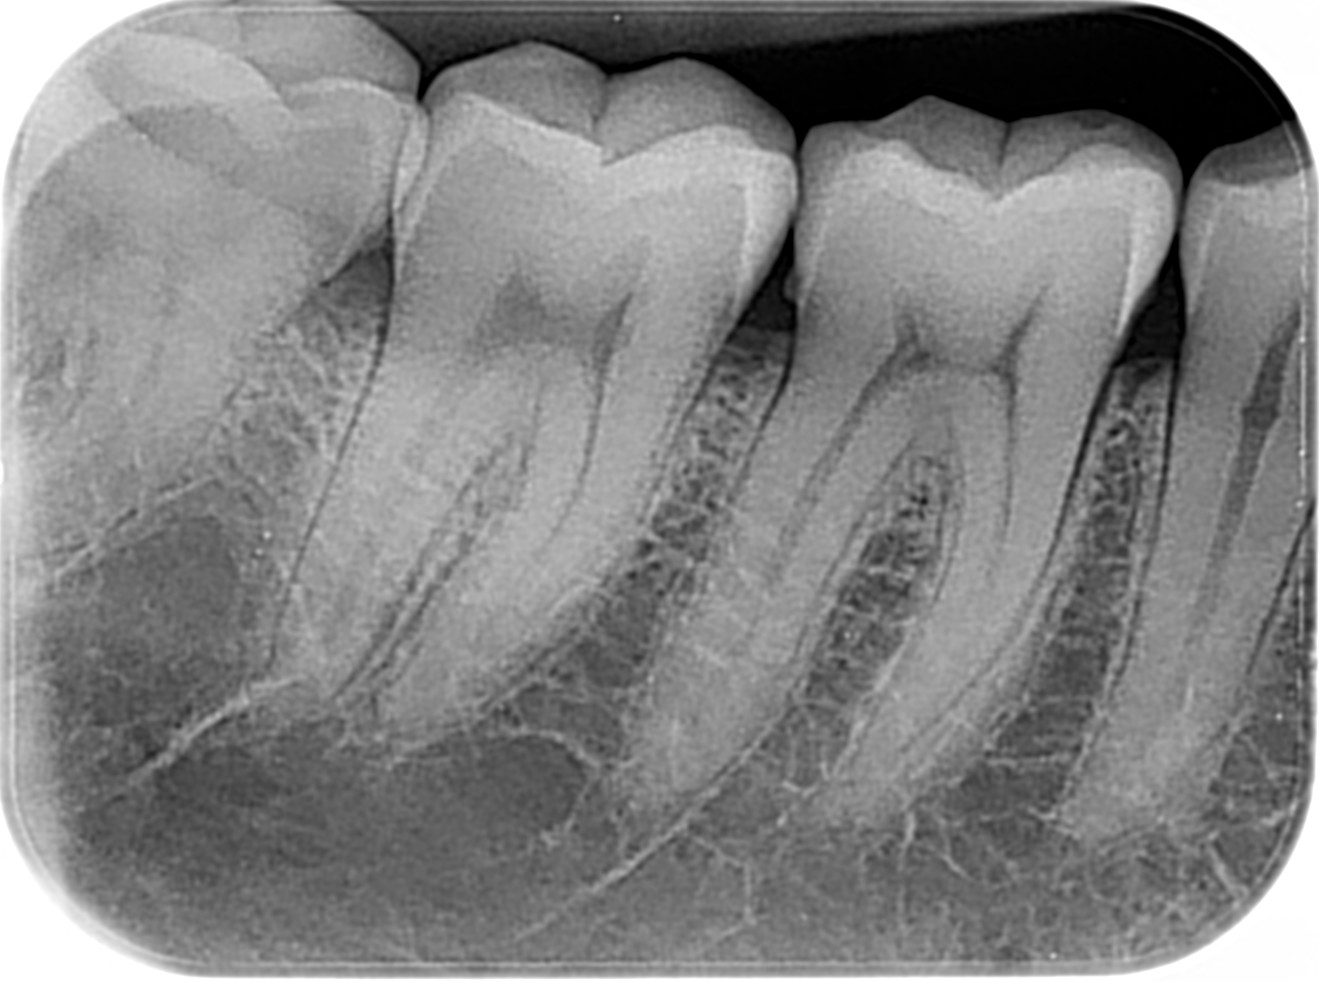

Radiografía Bitewing

Bitewing Bilateral

Propósito principal detección de caries: Es la herramienta "Gold standard" para encontrar caries que no son visibles a simple vista, especialmente en áreas de contacto (premolares y molares) y visualizar desajustes cervicales.